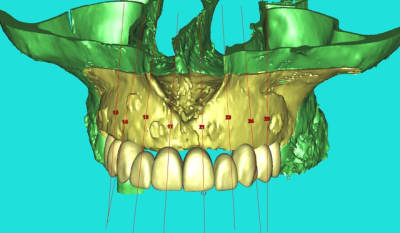

dentiste57 écrivait:

--------------------

> et là ?

> greffe selon ta méthode ?

Cross section dhvkc8 - Eugenol

3d dt3qom - Eugenol

Overview uqcp6u - Eugenol

S2y2o1v7q53ws4r5wy6ou8czrpom - Eugenol

pxav

01/05/2011 à 12h55

> dentiste57 écrivait:

> --------------------

> > et là ?

> > greffe selon ta méthode ?

expansion, c'est plus cool!